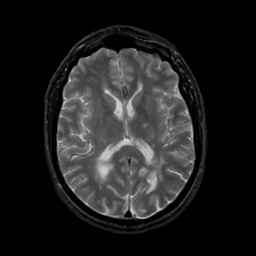

MR Study #20 October 6, 1991 -- Slice #28

[Home][Help][Clinical][Tour 1][Tour 2] Slice 28